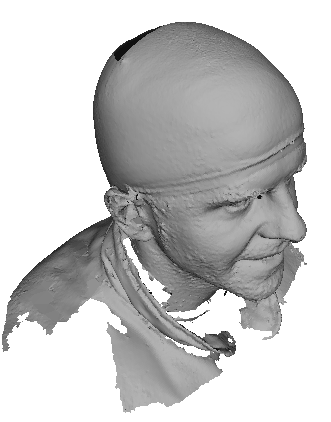

Toolsets to define normal appearance and therefore both assist with planning of surgery and define optimal outcomes from a range of surgical interventions are currently either crude or lacking. Therefore, the unit collected a large, high quality 3D image dataset of 1523 human heads. An example is given in Fig. 1 showing the 3D channel only on the left, and the 3D data with texture pasted on on the right. The data was collected over well-conserved demographics, and an age range of 1 to 89 years, see Fig. 2. The dataset was collected with the aim of developing a normal equivalent of the human cranium and face in order develop the tools to enhance patient experience following surgery. We plan to make the dataset publicly available in the near future.

An overview of our approach is shown in Fig 3. We firstly describe this process in brief in this section, and then in later sections give more detail on each stage, with examples of output results from each stage. Note that the outputs are both a 2D profile model of the face and cranium (close to the bilateral symmetry plane, also known as the sagittal plane) and a full 3D head model. First we explain the group of processes that generate a landmarked, pose normalised head. These are shown on the left of Fig. 3.